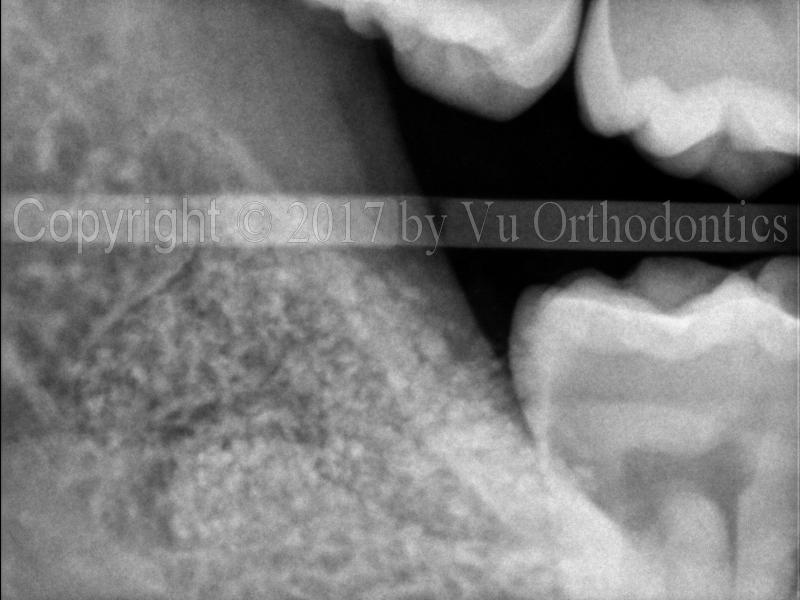

The following example shows a case of an orthodontic patient that needs four premolars extracted. In this case, saving wisdom teeth is the right thing to do. Figure 1 shows an image of impacted wisdom tooth #17.

Fig. 1 Impacted wisdom tooth #17